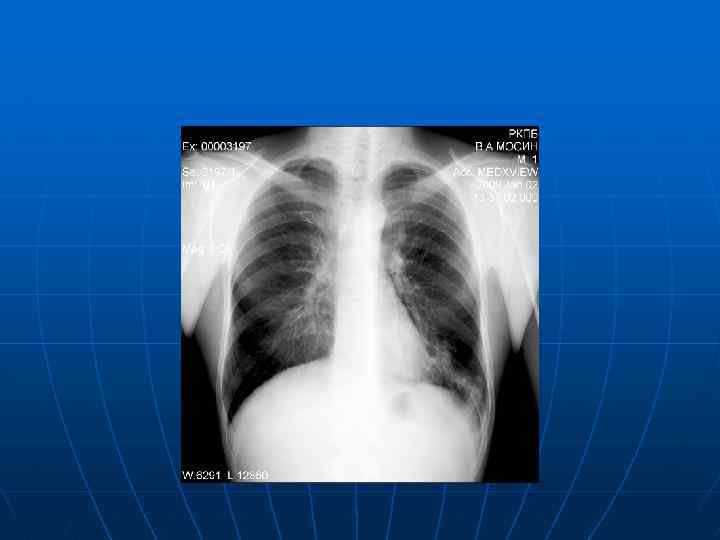

К своевременно выявленным больным у взрослых относятся: больные с неосложненными формами первичного туберкулеза, очаговым, инфильтративным, ограниченным диссеминированным туберкулезом. Давность заболевания в этих случаях обычно невелика, клинические симптомы туберкулеза не выражены, заболевание протекает относительно легко. Протяженность поражения небольшая, процесс не выходит за рамки двух сегментов, деструктивные изменения на обзорной рентгенограмме не определяются. Бактериовыделение отсутствует или скудное (единичные МБТ при культуральном методе исследования), поэтому такие больные не представляют серьезной эпидемической опасности для окружающих. При адекватной лечебной тактике вероятность клинического излечения с формированием минимальных остаточных изменений очень высока.

К несвоевременно выявленным у взрослых относятся больные: с осложненными и распространенными формами первичного, диссеминированного и вторичного туберкулеза, включая осумкованный плеврит и эмпиему. Давность заболевания и распространенность туберкулезного воспаления довольно значительные (поражено 3 сегмента и более). На обзорной рентгенограмме выявляются явные признаки деструкции. Бактериовыделение массивное, поэтому эпидемиологическая опасность больных очень велика. Обратное развитие туберкулезного процесса на фоне лечения происходит медленно, возможности для достижения его высокой эффективности ограничены. Клиническое излечение часто сопровождается формированием больших остаточных изменений, что повышает риск рецидива туберкулеза. О позднем выявлении больного свидетельствует обнаружение далеко зашедшего патологического процесса – фиброзно-кавернозного, хронического диссеминированного туберкулеза и/или эмпиемы плевры. К поздним случаям выявления туберкулеза также относятся его остропрогрессирующие формы (казеозная пневмония и милиарный туберкулез).